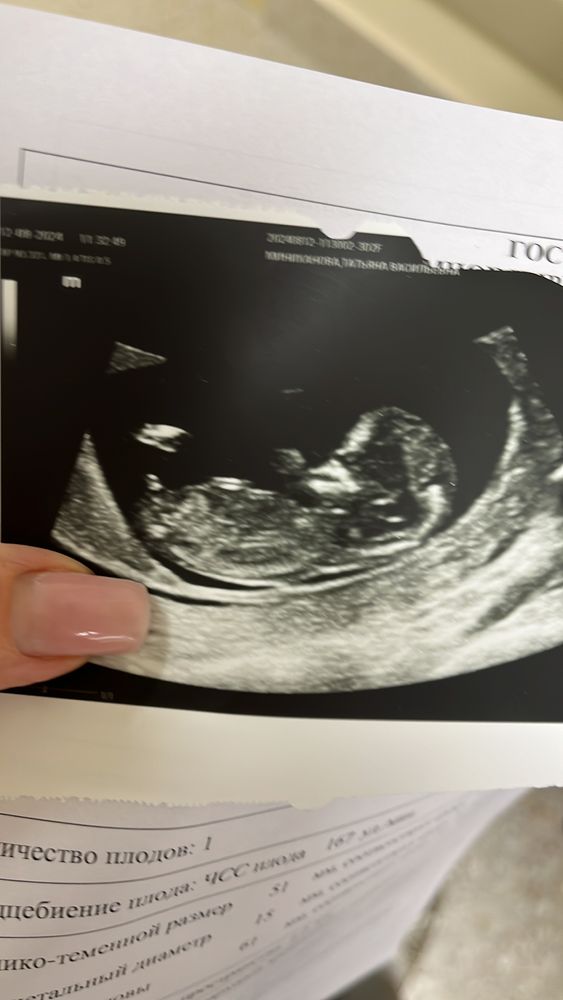

Пол ребенка в 12недель?

Таня, тут прямо очень хорошо видно что мальчик, у моей было совсем по другому, половой бугорок вдоль позвоночника, а у вас вверх 🤭 поздравляю вас с мальчишечкой 💙 растите крепкими, родов вам в срок🤞🏻☺️